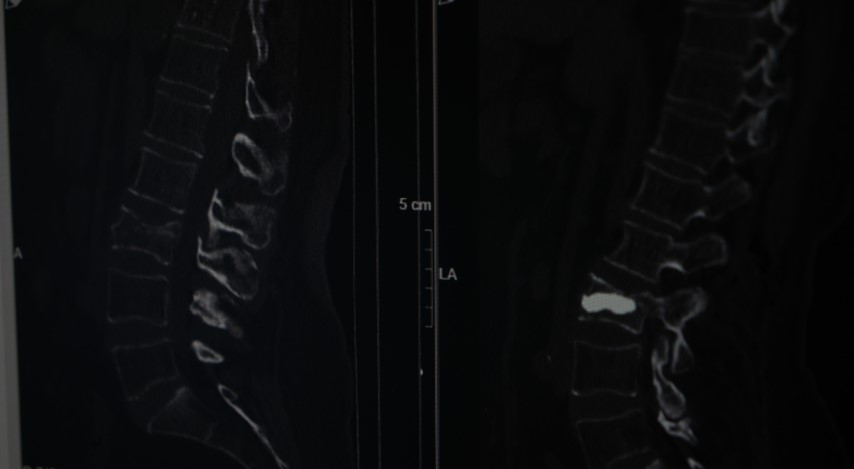

"Omurga kırıklarını menopoz sonrası bayanlarda sıklıkla görüyoruz" diyerek sözlerine başlayan Doç. Dr. Evran, "Bu hastalarda travma sonrası kemik yoğunlukları düşük olduğu için omurgalarında kırık oluşma ihtimali normal popülasyona göre çok daha fazla görülüyor. Travma geçiren menopoz sonrası bir insanda kemik yoğunluğuna daha önce dikkat etmemiş, bununla ilgili daha önce tedavi almamışsa bu hastalarda travma sonrası oluşan, bel, sırt, boyun ağrılarında özellikle bu kırıklar düşünülmekte. Bir beyin ve sinir cerrahisi hekimine başvurmaları önerilmekte. Vücudun daha çok yük taşıyan bel ve sırt bölgelerinde oluşuyor. Hasta sırt veya bel ağrısıyla travma sonrası başvurduğu zaman önce gerekli tetkiklerini yapıyoruz. Görüntülemelerinde kırığı tespit etmiş olursak ve bu bir travma sonrası gelişen bir kırıksa bu kırıkta öncelikle omurgadaki çökme miktarının derecelerine bakıyoruz. Derecelere göre korse, yatak istirahati gibi tedavileri öncelikle deniyoruz. Fakat kırığın çökme derecesi çok ileriyse veya omuriliğe bir zarar söz konuysa daha minimal invaziv olarak tedaviler ve daha ileri hastalarda cerrahilerle omurgaya enstrümantasyonlarla tedavi edebiliyoruz" dedi.

Tedavi seçeneklerine yönelik konuşan Doç. Dr. Evran, "Hastanın klinik durumu uygunsa vertebroplasti veya kifoplasti dediğimiz halk arasında omurgaya çimento doldurma olarak bilinen işlemi bu hasta grubunda uygulamak öncelikli tercihimiz oluyor. İşlemin bazı avantajları var; eskiden bu tarz kırıklarda hastaları günlerce yatakta yatırıp hatta tüm vücut alçıya alınıp tedavi edilirmiş ama günümüzde teknolojinin de ilerlemesiyle artık bu yöntemler daha ön planda. Vertebroplastide hastanın cildinde büyük bir kesi olmadan sadece bir iğnenin geçtiği kadar bir delikten iğne yardımıyla girilerek omurganın içine bazen tek bazen çift taraflı girilerek başlangıçta içinde sıvı olan sonra katılaşan bir maddeyi enjekte ediyoruz. Omuriliğin içinde donuyor. Başka bir yöntemi olarak da bazen omurganın içinde bir balon yardımıyla balon şişirerek omurganın eski yüksekliğini kazanmasına ve daha güvenli bir alan oluşturarak balonun şiştiği alana çimento dediğimiz şeyle doldurarak hastanın da ağrılarının geçmesini sağlamış oluyoruz, akşamına hasta taburcu edilebiliyor" diye konuştu.

Sözlerini sürdüren Doç. Dr. Evran, "Bu tarz hastalar kliniğimize çok başvuruyor sadece kliniğimize değil Türkiye hatta dünya genelinde bu tarz hastalar çok fazla. Bu cerrahiyi uyguladığımız ayda ortalama 4 ila 5 hasta. Bu hastamızda bir travma sonrası bel omurgasında kırık meydana gelmiş, ilk planda kırık olarak algılamıyor, şiddetli ağrılardan vücudunda kötü bir şey geliştiği yönünde bir kanaate varmış. Ameliyat sonrası 4’üncü saat, ayağa kalkarak yürümesini sağladık. Osteoporoz olan hastalarda omurga kırıklarını önlemenin yollarından bir tanesi de menopoz sonrası bayanların mutlaka kemik yoğunluğuna baktırması gerekiyor. Hastalar bu tarz travmalardan sonra ağrılarını birçok şeye yorabiliyor. Özellikle bel fıtığı, belinde kas güçsüzlüğü, düzleşme gibi hastamız da önce bel fıtığından şüphelenerek ağrılarının ona bağlı olduğunu düşünmüş fakat dirençli bir ağrı. Hiçbir medikal tedavi, ilaçla ağrıları dinmeyince durumun daha farklı boyutta olduğunu düşününce hastanemize başvurmuş" dedi.